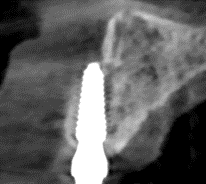

3/ Bước 3: Giai đoạn cấy ghép implant

Chuẩn bị răng tạm cố định 1 ngày sau phẫu thuật

Gắn răng tạm cố định 1 ngày sau phẫu thuật

X-Quang ngay sau gắn răng tạm cố định